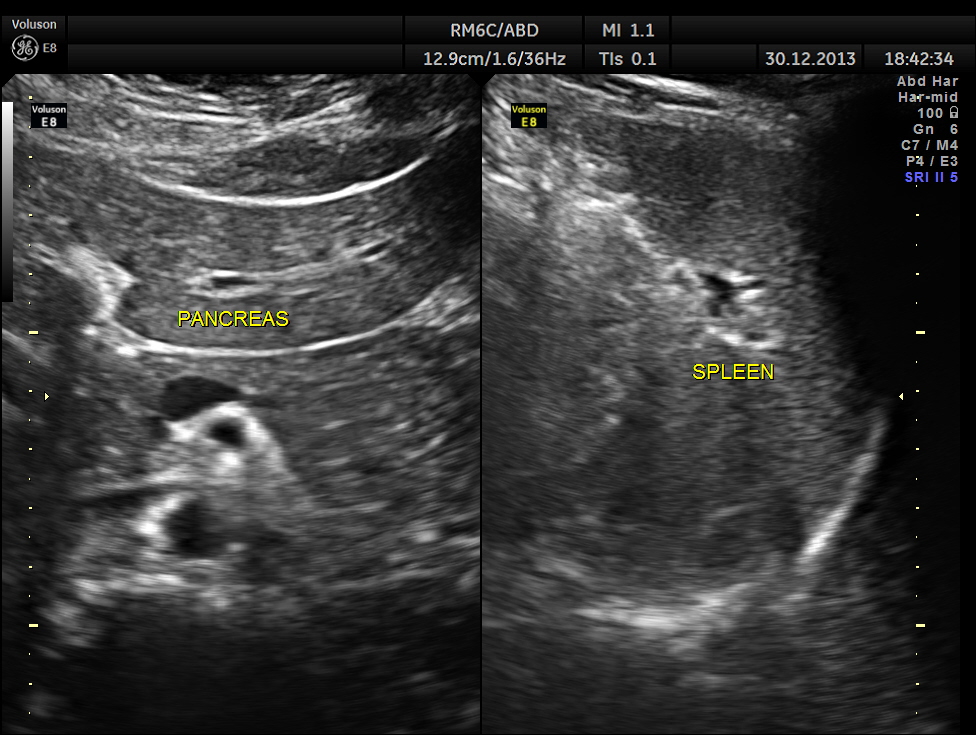

Pancreas and spleen were normal.